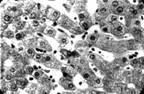

Рис. 2. Вид

изотопной гепатограммы у больного с регионарным

подведением лекарственных средств непосредственно к

печени через реканализированную пупочную вену.

При морфологических исследованиях прижизненных пунктатов печени выявлено, что в 1-е сутки после ожога у

всех обнаруживался отек паренхимы и субкапсулярного

слоя печени. На гистологических препаратах видны явления лимфостаза,

образования больших застойных лакун в лимфатическом коллекторе. Дольчатое

строение печени и трабекулярная структура долек

нарушались за счет дискомплексации печеночных балок

(рис. 3).

Своевременное

отведение лимфы из ГЛП устраняло застой в печени. Прижизненная пункционная

биопсия печени на 3-5 день после дренирования ГЛП с последующим гистоморфологическим

исследованием показала, что, устраняя застой лимфы в

печени, лимфатикостомия способствовала

интерстициальной дегидратации печени, "высушивала" пространства Диссе и Малла. Эндотелий

капилляров, отслоенный от поверхности печеночных балок до наружного отведения

лимфы из ГЛП, после дренирования тесно прилегал к поверхности печеночных балок.

Восстанавливалась архитектоника печеночных балок. Наружное отведение лимфы в

лечении обожженных устраняло микроциркуляторные нарушения в печени и портальной

системе (рис. 4).

Рис. 3. Патологогистоло-гическое исследование N 4843, больного Б.

на 6 день после ожога перед дренированием ГЛП

Рис. 4. Патологогистоло-гическое исследование N 4562, больного Б.

через 5 дней после дренирования ГЛП и наружного отведения лимфы

из главного лимфатического коллектора